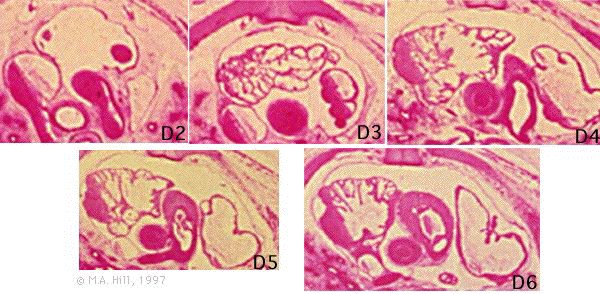

Extract from the 27mm Human serial section series. Clicking on each section will take you to the labelled image.